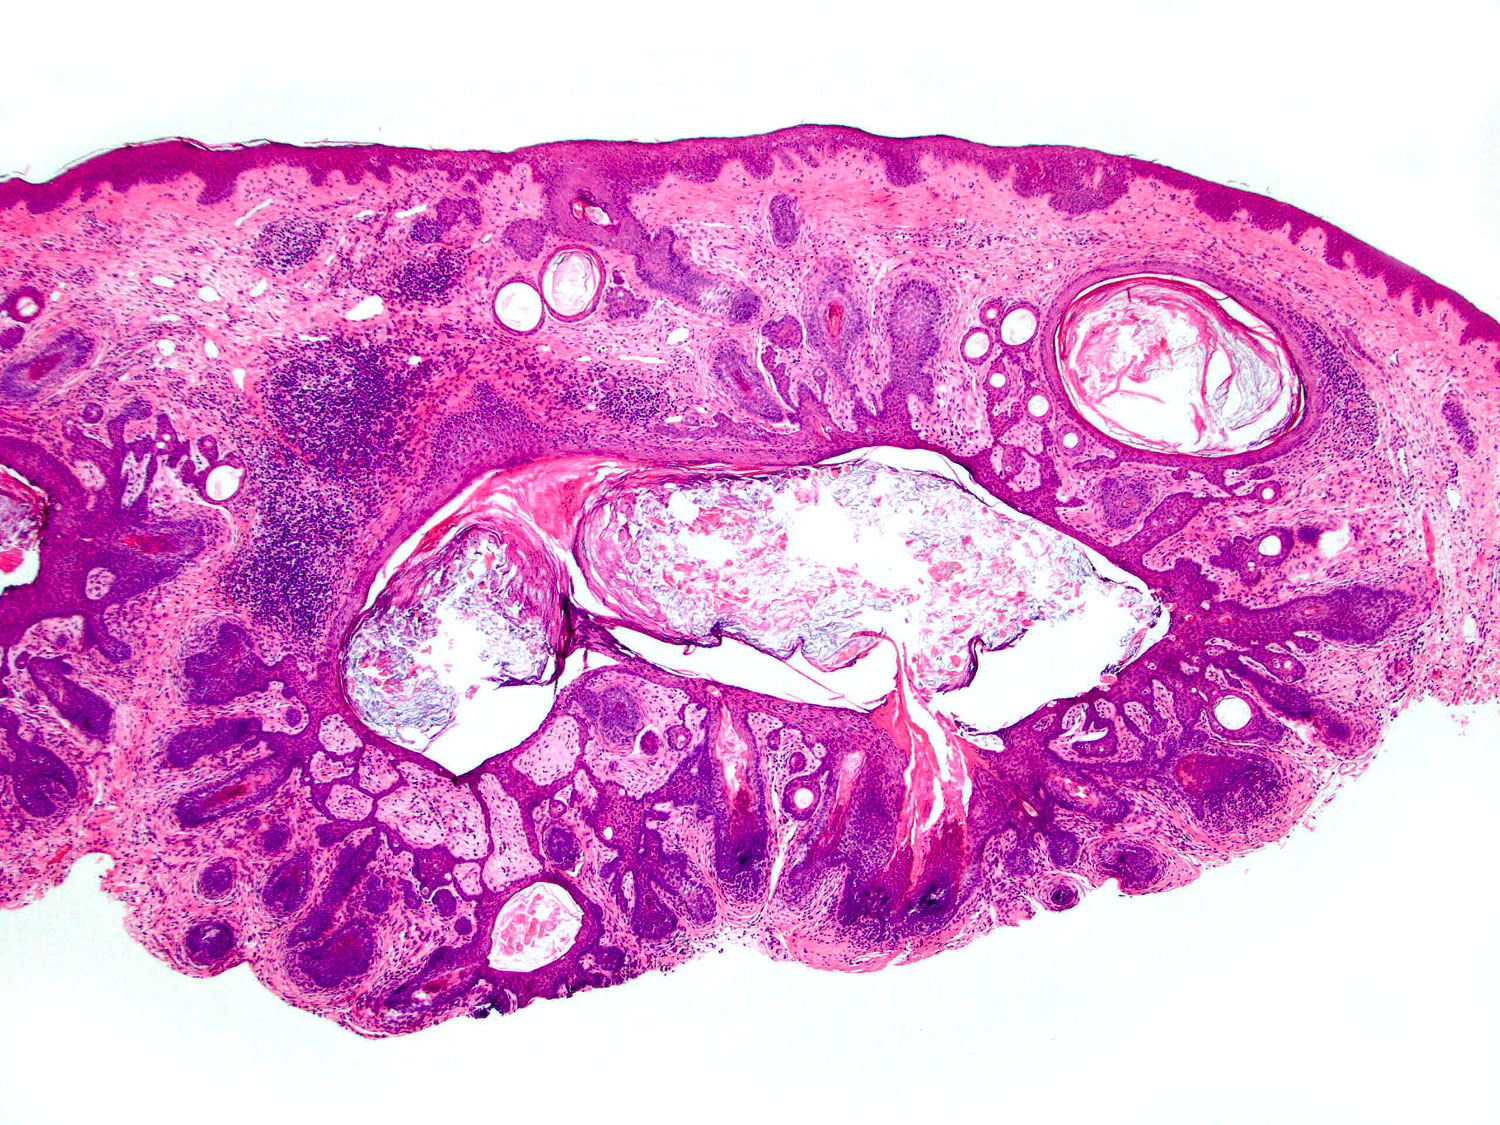

H&E staining (4x objective)